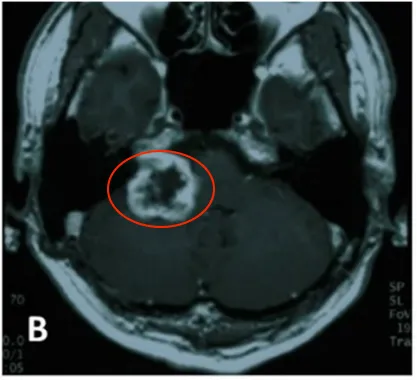

2004年5月,患者确诊为听神经瘤并接受首次开颅手术。术后病理检查确认诊断,初期治疗显示右侧桥小脑角区肿瘤呈现不均匀强化表现。为控制术后残留病灶,2005年8月实施伽玛刀治疗。2007年5月随访发现肿瘤再次进展,遂行第二次开颅手术。

2004年4月初始MRI显示右侧桥小脑角区肿瘤不均匀强化。2005年8月首次术后、伽玛刀治疗前影像资料记录肿瘤状态。2007年5月第二次术前MRI评估显示肿瘤进展,术后一个月影像确认切除范围。